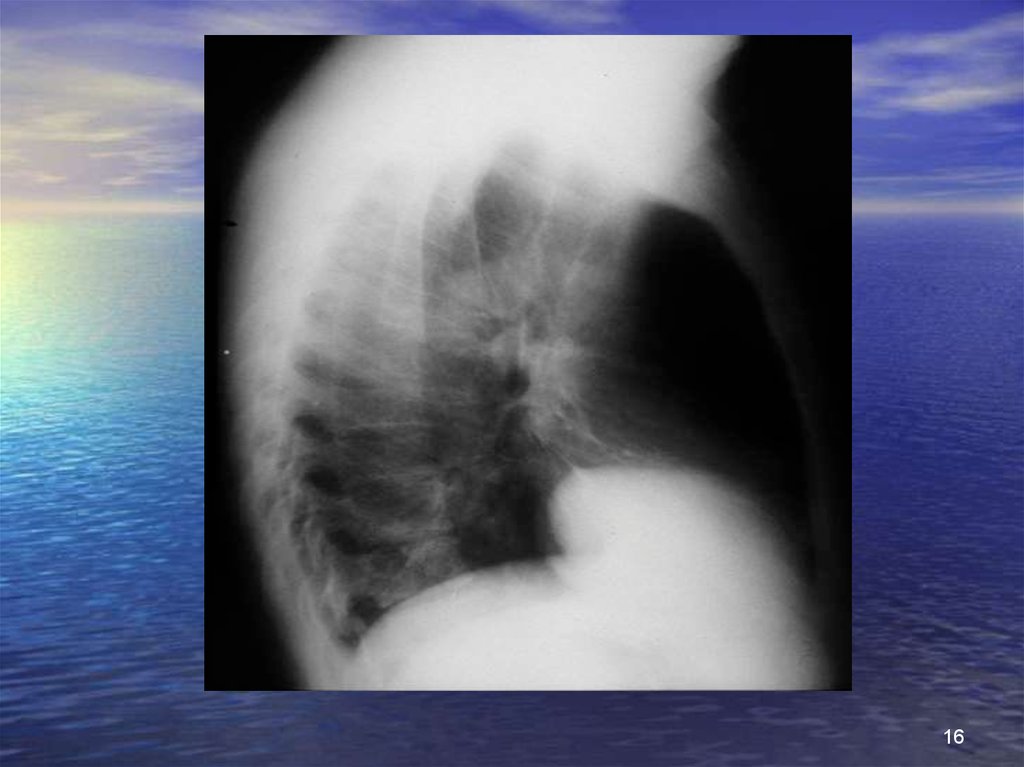

16.

16